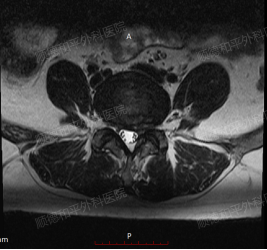

辅助检查:腰椎磁共振是重要的检查手段,可清晰显示椎间盘变性、膨出或突出,以及是否压迫硬脊膜囊、椎管、侧隐窝及椎间孔等。李女士的腰椎磁共振显示L4/5、L5/S1椎间盘存在变性、膨出并突出,且有相应的压迫情况,为诊断提供了有力依据。

术前&术后